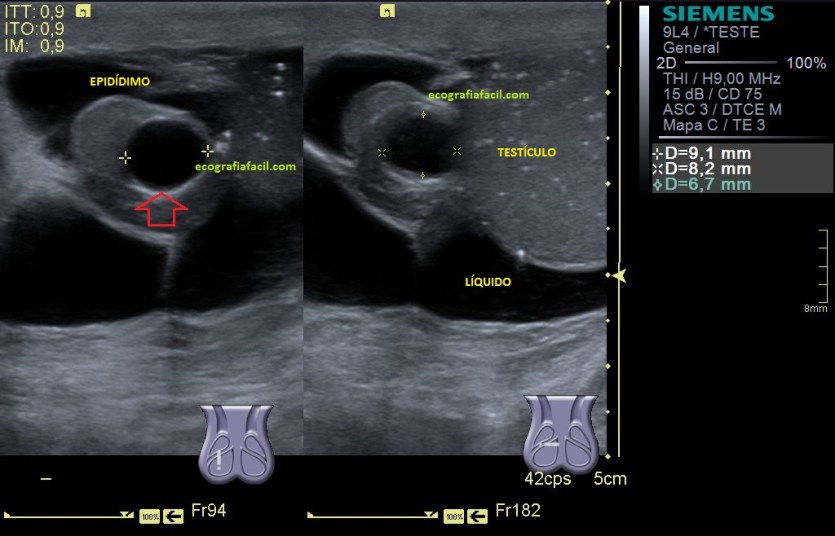

La imagen 3 y 4 son parte estudian en eje largo y corto las medidas de la lesión en los tres ejes del espacio, en ocasiones, podemos tener más de una lesión. Siempre super atentos si las lesiones son intra o extratesticulares.

Quistes: Las lesiones quísticas no son uniformemente benignas debido a que los tumores testiculares pueden sufrir

degeneración quística a causa de una hemorragía o una necrosis, pero habitualmente, los quistes (flecha roja), anecoicos, redondos, en número indeterminado y en la cabeza epididimaria son muy habituales y benignos (imagen 9), su tamaño también es variable.